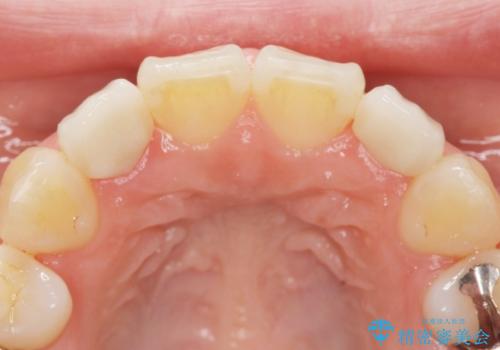

矮小歯 セラミッククラウンで綺麗に 30代女性

全顎的に歯並びにがたつきがあり、上の側切歯(上顎両側2)は生まれつき小さい歯(矮小歯)でした。

矯正治療後、矮小歯をセラミッククラウンにより理想的な歯の大きさに仕上げました。